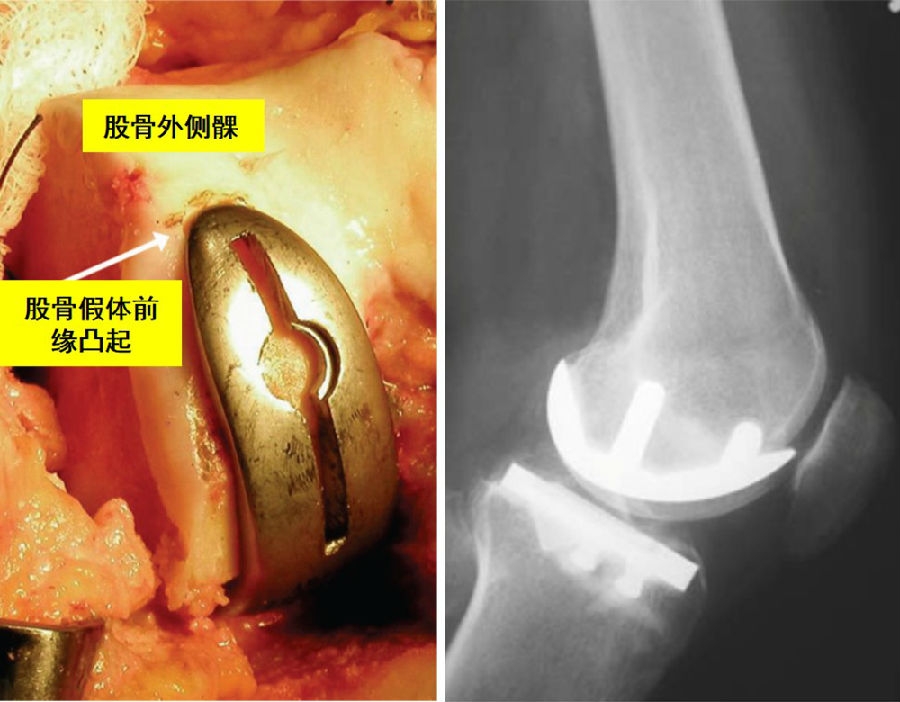

避免:股骨假体过屈,前缘凸起,发生髌骨撞击

避免:股骨假体过伸,前缘嵌入,发生髌骨弹跳

理想假体位置 A.股骨假体 胫骨假体中心线一致;B.股骨假体固定栓与后侧皮质呈35-40°

理想假体位置即前缘平稳过渡,后缘包容很好且不超出。